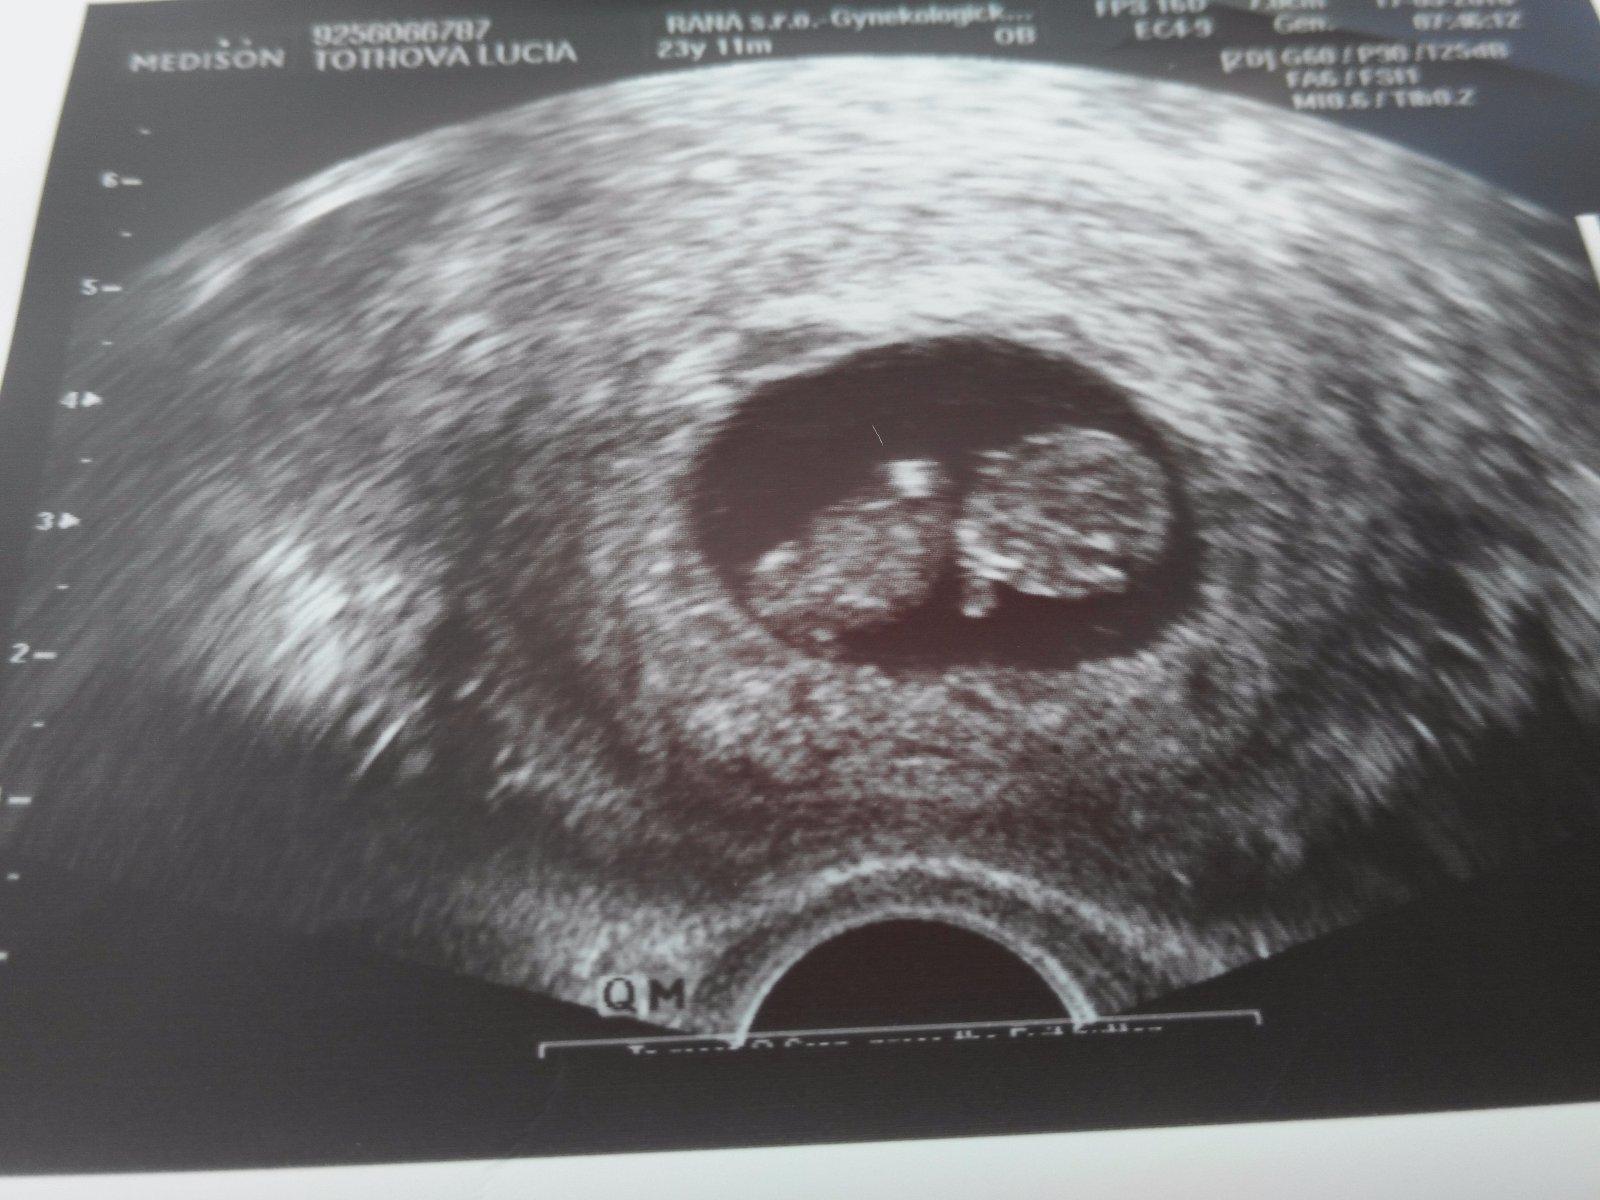

Chcem sa aj ja podelit o nasu obrovsku radost....som v 11 tyzdni a nas pokladik krasne rastie...termin mam 11. Decembra...a neviem sa uz dockat najblizsej poradni....uzivajte si tehotenstvo kocky ☺

ahojte baby zacinam 11tt a tiez sa vytesujem ze je vsetko ok..

takže s veľkou radosťou, aj ke´d zatiaľ s obavami sa ku Vám pridávam. Som v 8om týždni, som na PN ale nikomu ešte nevravime že sme tehu, lebo so po 2 potratoch, takže radšej tíško čakáme.